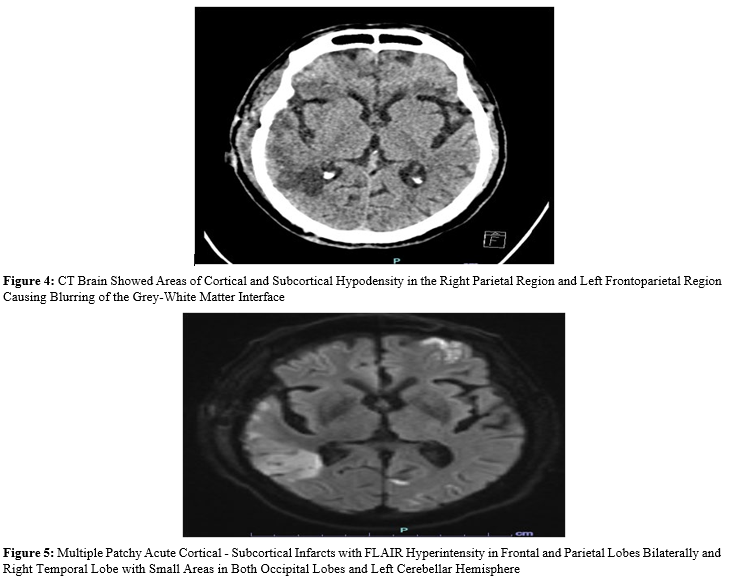

Patient underwent right FTP mini craniotomy and clot evacuation. On post-operative day 2 patient had a seizure and hyponatremia with serum Na 127 meq/L which was managed conservatively. On post-operative day 6 patient developed severe sepsis and was electively intubated due to breathing difficulty. Patient developed transient hemiparesis lasting for 24 hours. CT Brain done showed multiple hypodensity areas in frontal, temporal and parietal region. MRI Brain revealed acute cortical - subcortical infarcts in frontal and parietal lobes bilaterally and right temporal lobe with small areas in both occipital lobes and left cerebellar hemisphere.

MR Angiogram showed normal circle of Willis vessels. No signs of arterial occlusion. MR Venograms showed no Dural venous sinus thrombosis. Echocardiography (LVEF 50%). LP was done. CSF showed raised count 1000 leukocytes (85% polymorphs), 1 mg/ dl glucose and 400 mg/dl proteins. CSF culture grew citrobacter koseri. Systemic cultures were sent. Patient was started on iv meropenem. On postoperative day 10. Patient had a asystole for which CPR was given. Patient was revived. Patient was continued on antibiotics. Patient underwent tracheostomy and was slowly weaned off from the ventilatory support and discharged.